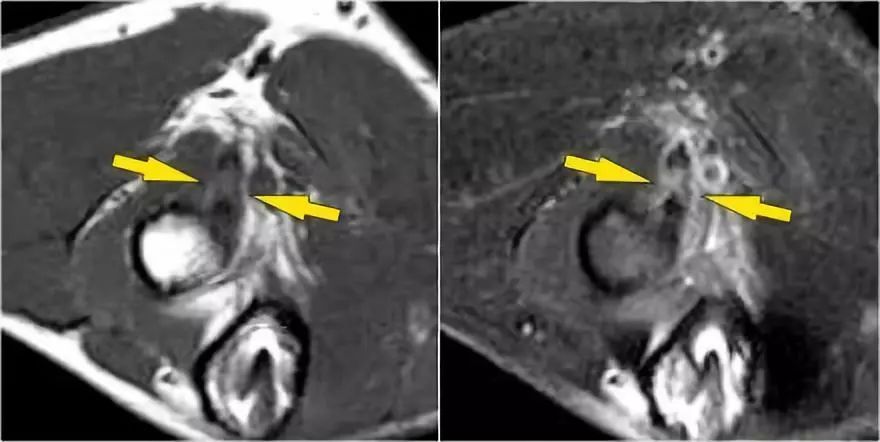

下面的图像,请注意,前束是完整的,并牢固地附着在崇高的结节上(黄色箭头)。在接下来的两张图像上,有一些软组织水肿,后面有更多异常信号(红色箭头)。所以我们怀疑后束的病理学。现在你记得轴向图像可能会有所帮助。

在下面轴向图像上,我们很好地看到前束是o.k. (红色箭头)。它旁边只有一些水肿。

然而,后束不是o.k,有一部分撕裂。这种情况我们偶尔会在投掷运动员中看到,前束完整,肘部不稳定。他们以某种方式撕裂了他们的后束,导致疼痛。他们不需要手术,但它仍然可能让他们在游戏中停留很长一段时间。